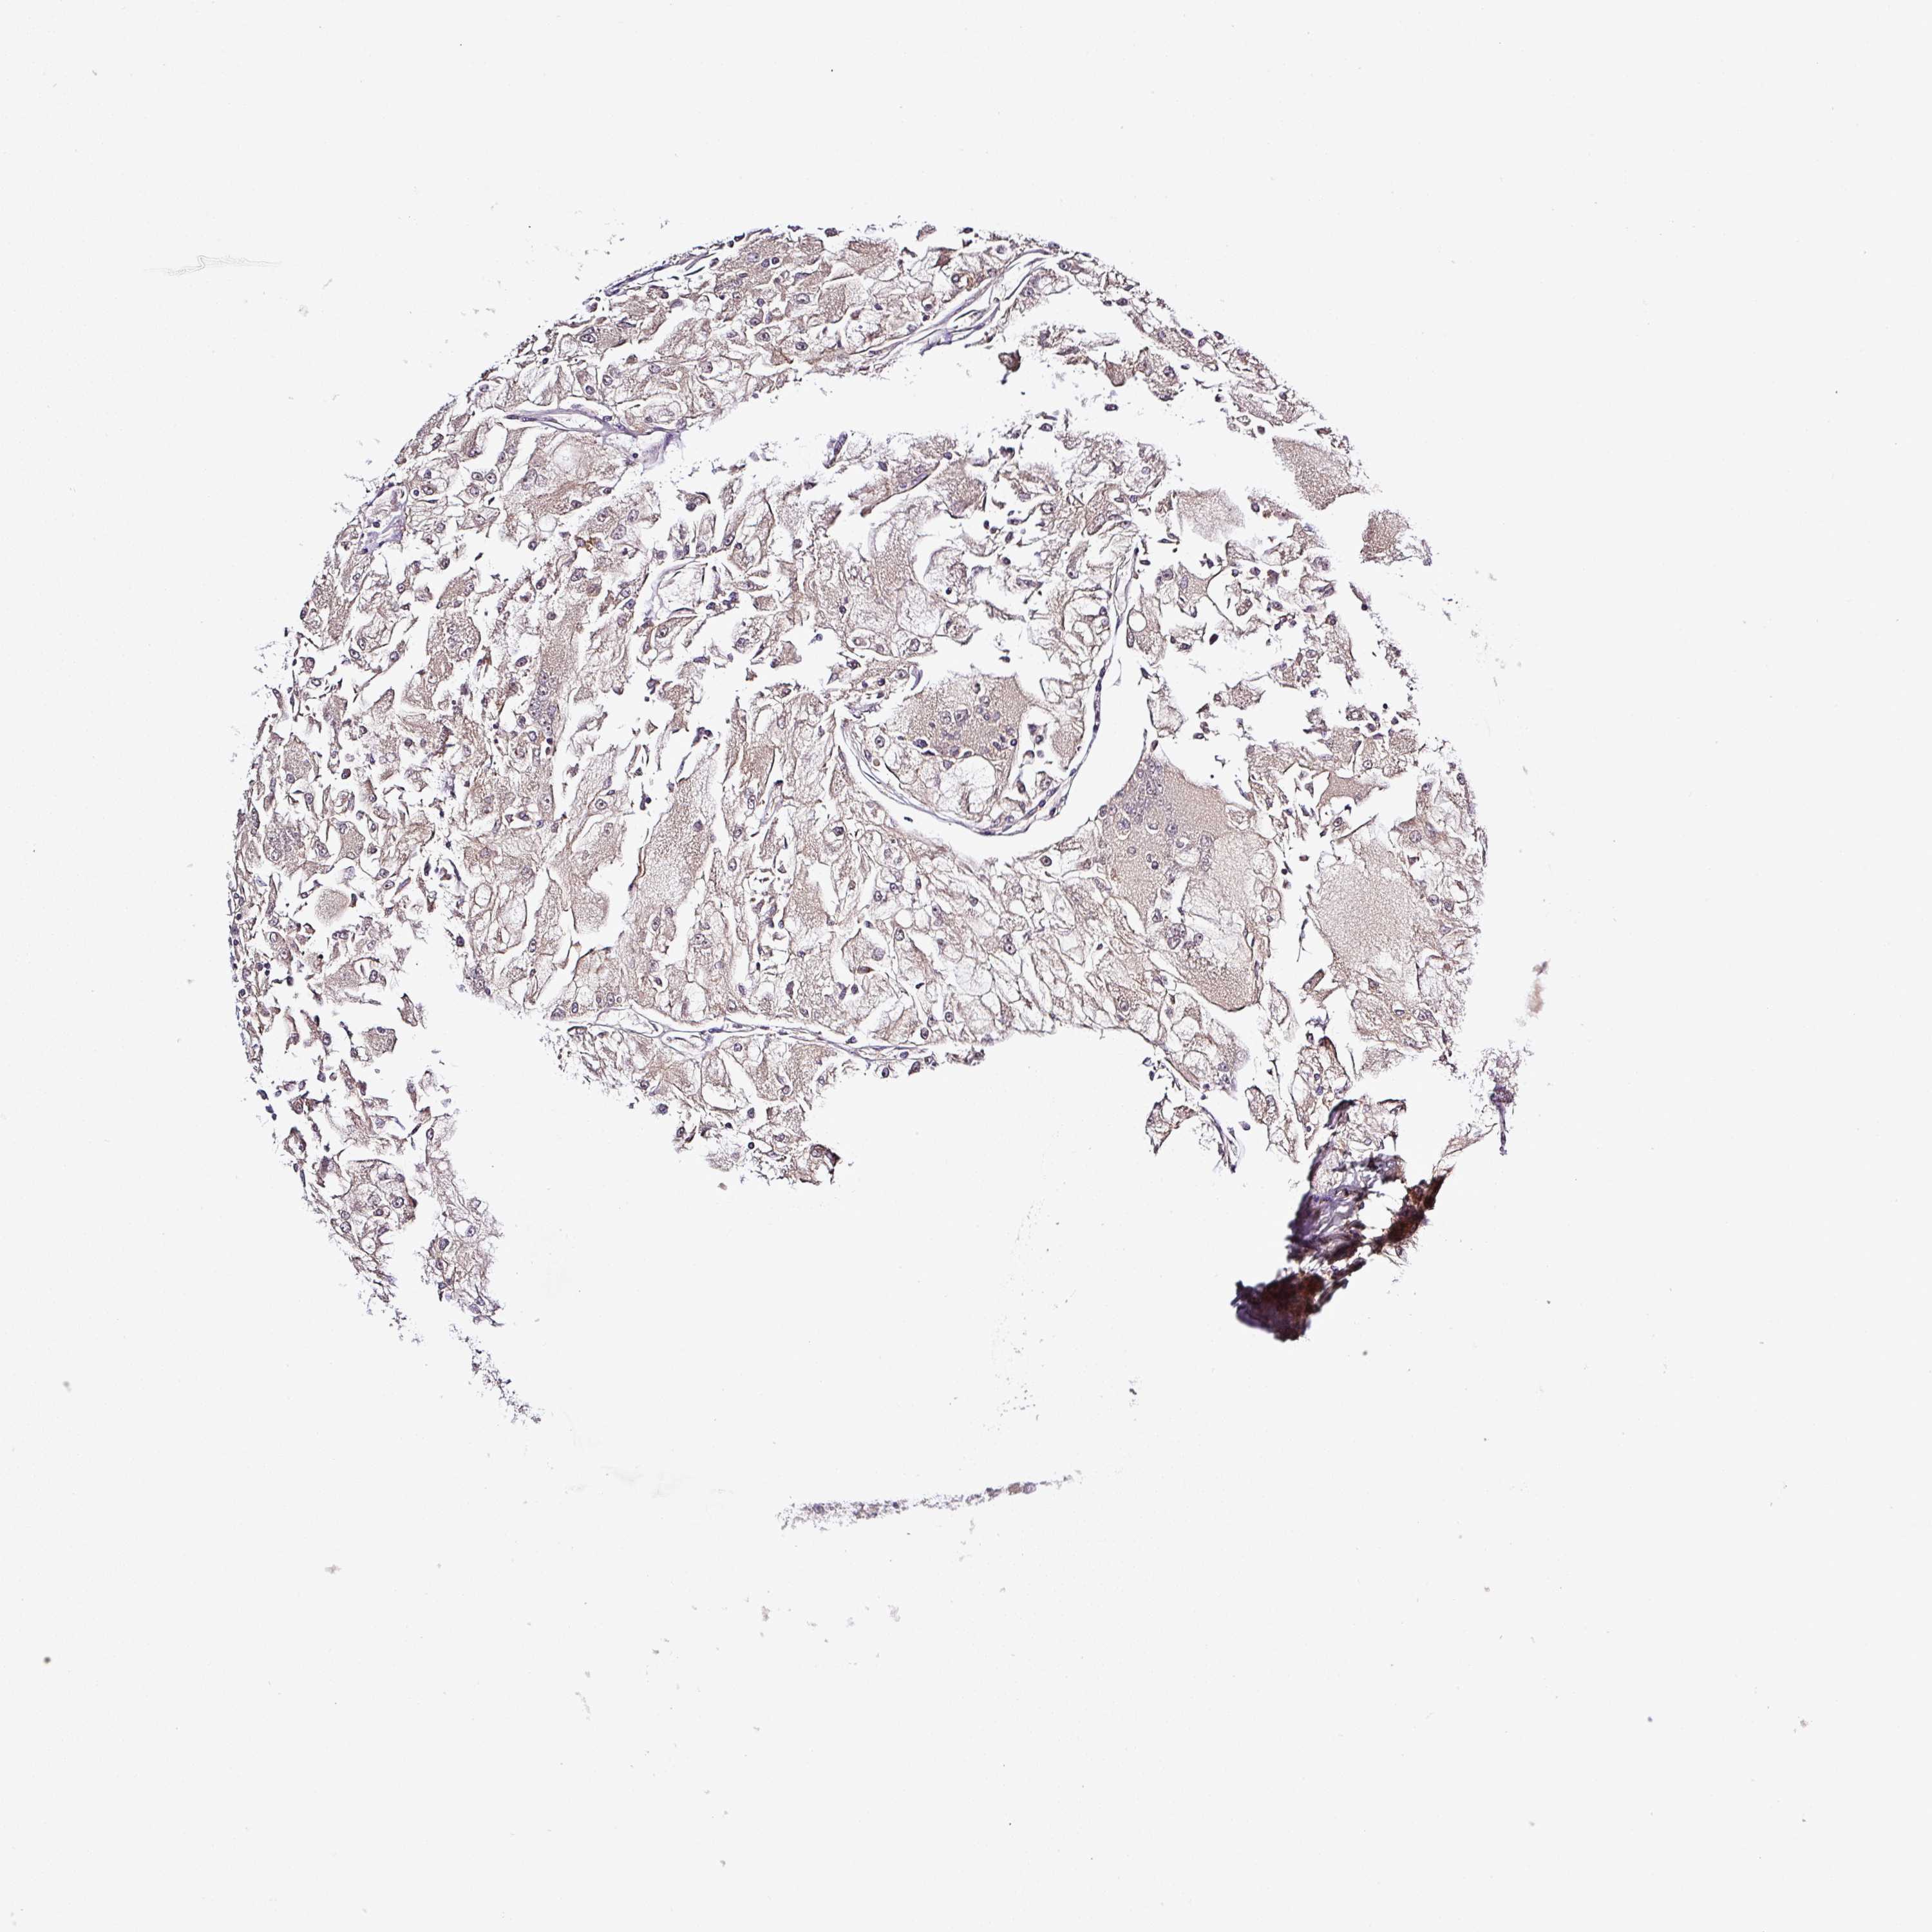

KIDNEY RENAL CLEAR CELL CARCINOMA (VALIDATION) - Interactive survival scatter ploti

The Survival Scatter plot shows the clinical status (i.e. dead or alive) for all individuals in the patient cohort, based on the same data that underlies the corresponding Kaplan-Meier plots. Patients that are alive at last time for follow-up are shown in blue and patients who have died during the study are shown in red.

The x-axis shows the expression levels (FPKM) of the investigated gene in the tumor tissue at the time of diagnosis. The y-axis shows the follow-up time after diagnosis (years). Both axes are complimented with kernel density curves demonstrating the data density over the axes. The top density plot shows the expression levels (FPKM) distribution among dead (red) and alive patients (blue). The right density plot shows the data density of the survived years of dead patients with high and low expression levels respectively, stratified using the cutoff indicated by the vertical dashed line through the Survival Scatter plot. This cutoff is automatically defined based on the FPKM cutoff that minimizes the p-score. The cutoff can be changed by dragging the vertical line or by entering a cutoff value in the square labeled "Current cut-off".

Under the Survival Scatter plot the p-score landscape (black curve; left axis) is shown together with dead median separation (red curve; right axis). Dead median separation is the difference in median mRNA expression between patients who have died with high and low expression, respectively. It is calculated as follows: median FPKM expression of dead patients with high expression - median FPKM expression of dead patients with low expression. This is intended to aid the user in visually exploring custom cutoffs and the associated p-scores and dead median separation.

Individual patient data is displayed and can be filtered by clicking on one or more of the category buttons on the top of the page. Categories describing expression level and patient information include: high, low, alive, dead, female, male and tumor stages. The scale of the x-axis can be toggled between linear and log-scale by clicking on the "x log" button. Mouse-over function shows TCGA ID, patient information and mRNA expression (FPKM) for each patient.

& Survival analysisi

Kaplan-Meier plots summarize results from analysis of correlation between mRNA expression level and patient survival. Patients were divided based on level of expression into one of the two groups "low" (under cut off) or "high" (over cut off). X-axis shows time for survival (years) and y-axis shows the probability of survival, where 1.0 corresponds to 100 percent.

ZNF513 is not prognostic in Kidney Renal Clear Cell Carcinoma (validation)

Best expression cut offi

Based on the FPKM value of each gene, patients were classified into two groups and association between prognosis (survival) and gene expression (FPKM) was examined. The best expression cut-off refers the FPKM value that yields maximal difference with regard to survival between the two groups at the lowest log-rank P-value. Best expression cut-off was selected based on survival analysis .

When clicking on this number, the vertical dashed line indicating cut-off, the interactive survival plot, and the Kaplan-Meier curve will be adjusted to show results based on the best expression cut-off.

: 17.25

P scorei

Log-rank P value for Kaplan-Meier plot showing results from analysis of correlation between mRNA expression level and patient survival.

N/A

5-year survival highi

5-year survival for patients with higher expression than the expression cutoff.

For melanoma and glioma, 3-year survival is shown.

5-year survival lowi

5-year survival for patients with lower expression than the expression cutoff.

TCGA RNA samplesi

RNA-seq data is reported as average FPKM (number Fragments Per Kilobase of exon per Million reads), generated by the The Cancer Genome Atlas (TCGA) .

Normal distribution across the dataset is visualized with box plots, shown as median and 25th and 75th percentiles. Points are displayed as outliers if they are above or below 1.5 times the interquartile range. FPKM values of the individual samples are presented next to the box plot.

Average pTPM 15.1

Number of samples 100